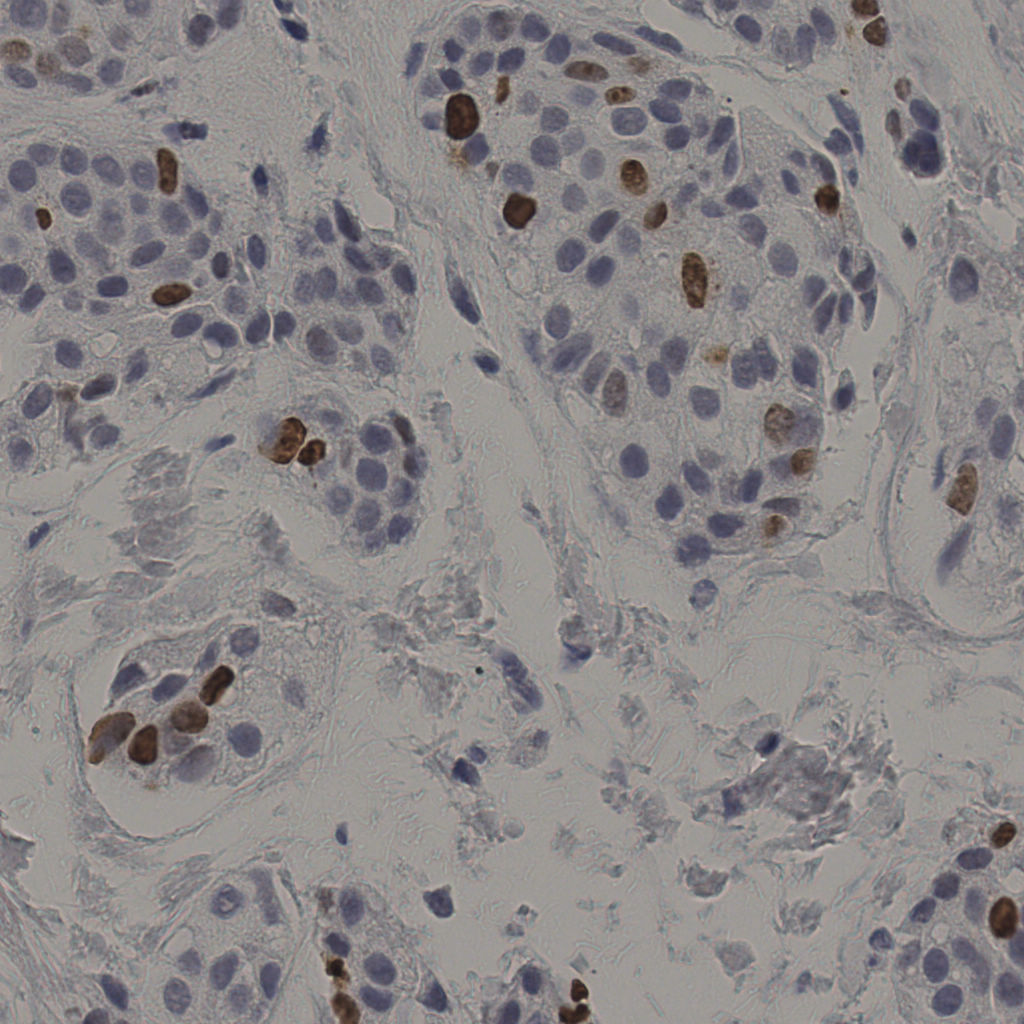

5.31%

Ki67 指数

阴 19502

阳 1093

缩略图

标记后

标记前